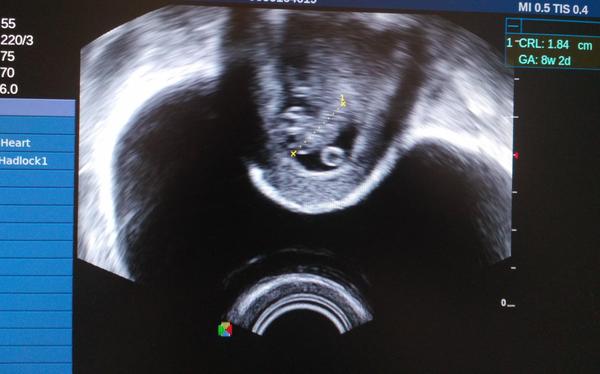

@omobinrin taky jsem u lékaře byla poprvé 9+0, ale podle ultrazvuku je mimco o 5 dní menší, ale srdíčko bylo krásně vidět 😍 a co se týče nevolnosti tak jsem je měla od 6 týdne do 9 týdne. Je to paráda, když už je mi dobře. Strašně jsem trpěla...